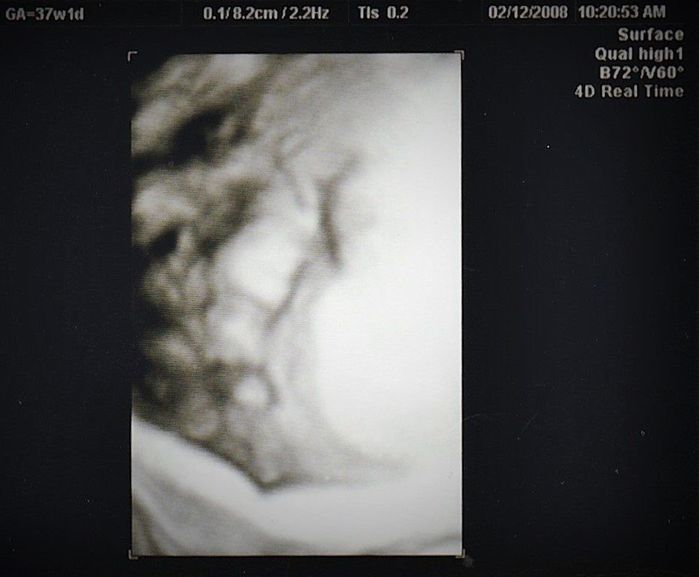

妊娠30週目のエコー写真

赤ちゃんの大きさは標準の真ん中あたり。胎盤の位置や羊水の量も正常、母子ともに問題はありませんでした。

ムチムチの赤ちゃんの顔がアップになった4D写真。出産まで3カ月をきり、改めて「出産準備をしなければ」と、焦り始めました。